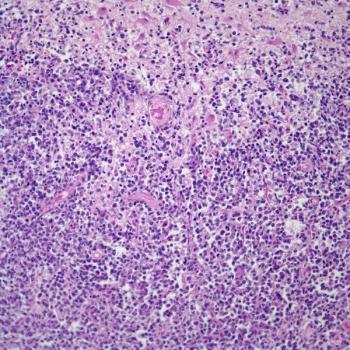

A 38-year-old woman presents with abdominal pain, and a biopsy is performed. What is your diagnosis?